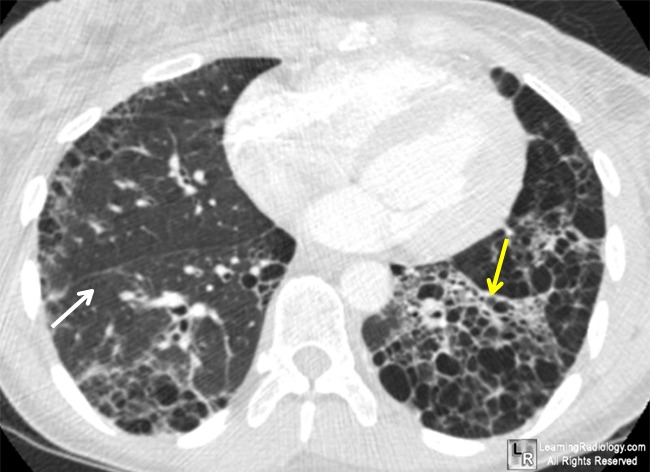

Lung

With pulmonary involvement, diffuse interstitial fibrosis, thickening of the alveolar membrane, and peribronchial and pleural fibrosis are observed. Bronchiolar epithelial proliferation accompanies the pulmonary fibrosis. Rupture of septa produces small cysts and areas of bullous emphysema. Small pulmonary arteries and arterioles show intimal thickening, fragmentation of the elastica, and muscular hypertrophy; this may occur without interstitial pulmonary fibrosis and produce pulmonary hypertension, particularly in a subset of patients with limited cutaneous SSc.